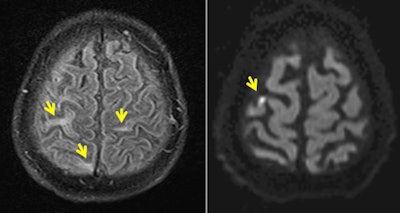

An MRI scan of the brain suggested meningoencephalitis, with "asymmetric white-matter hyperintensities on fluid-attenuated inversion recovery (FLAIR) imaging, multiple punctuated hyperintensities on diffusion-weighted sequences that were evocative of ischemic foci, and a slight hyperintensity of the right Rolandic fissure that was evocative of meningitis," noted the authors. CT also showed an irregular narrowing of the right callosomarginal artery.

MRI is always the first-line modality when dealing with suspected meningoencephalitis associated with infectious disease, explained Dr. Pierre Brugières, a senior neuroradiologist at AP-HP Henri Mondor who performed the patient's MRI with FLAIR and diffusion sequences.

"The main message is that in patients with Zika, radiologists should look for encephalitic lesions with MRI if central neurological deficits or consciousness disorder are observed. Morphological, diffusion-weighted imaging (DWI), and time-of-flight (TOF) sequences are key to diagnosis of meningoencephalitis which, if left undetected, would probably result in a worsening of impaired consciousness and death," Brugières told AuntMinnieEurope.com in an interview. "MRI allows us to check for brain infection by depicting parenchymal and subarachnoid space anomalies using FLAIR sequences. Furthermore, diffusion imaging may show subcortical ischemic stroke evocative of associated microvascular pathologies."